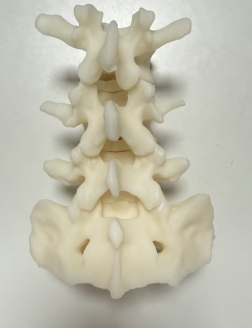

如果说UBE技术是脊柱治疗的“精准镜手”,那么3D打印技术就是定制化治疗的“私人裁缝”。针对每一位脊柱疾病患者的个体差异,医生通过高精度CT扫描,获取患者脊柱的三维立体数据,利用3D打印技术1:1还原脊柱的解剖结构——从椎体形态、椎间盘位置,到神经走行、病变范围,都能精准复刻,形成专属的脊柱模型。基于此模型,医生术前可以进行精准规划:模拟手术路径、预判操作风险、选择适配的内固定器械,甚至打印定制化的椎间融合器、内固定支架,确保手术操作“有的放矢”,贴合患者的个体解剖特征,避免传统手术中“凭经验操作”的不确定性,让脊柱治疗从“标准化”走向“个性化”,极大提升了手术的精准度与安全性。

1.术前规划更精准:通过3D打印脊柱模型,医生可直观掌握患者的病变细节,提前设计最佳手术路径,避开神经、血管等重要组织,降低手术风险;

2.术中操作更精准:在UBE高清内镜视野下,结合3D打印模型的术前预判,医生可精准切除病变组织、植入定制化内固定物,减少对正常脊柱结构的损伤;